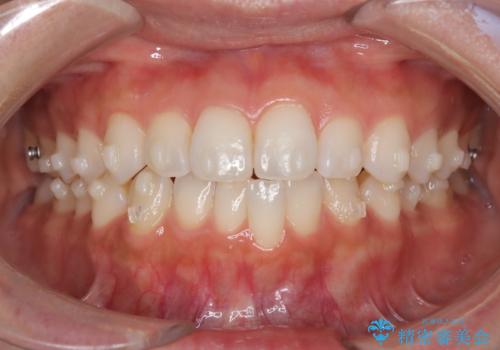

前歯の叢生を非抜歯で改善|インビザライン+IPR・遠心移動・FIX保定

- 前歯部のガタガタ(叢生)を非抜歯で改善するため、インビザラインによるマウスピース矯正を計画しました。抜歯は行わず、歯間をわずかに削るIPR(ディスキング)と奥歯を後方に移動させる遠心移動を併用して、歯を並べるスペースを確保します。歯列が整った後は、FIXリテーナー(固定式保定装置)で後戻りを防止し、安定した歯並びを維持します。

歯を抜きたくないというご希望に応え、インビザラインを用いて非抜歯で歯列を整えました。前歯に必要なスペースを確保するため、歯間をわずかに削るIPRと奥歯を後方に移動する遠心移動を組み合わせました。これにより自然で美しい歯並びを実現。治療終了後は、歯の裏側に目立たないFIXリテーナーを装着し、歯列の後戻りを効果的に防ぎました。患者様は治療中も審美的にストレスなく過ごされ、満足度の高い結果を得られました。